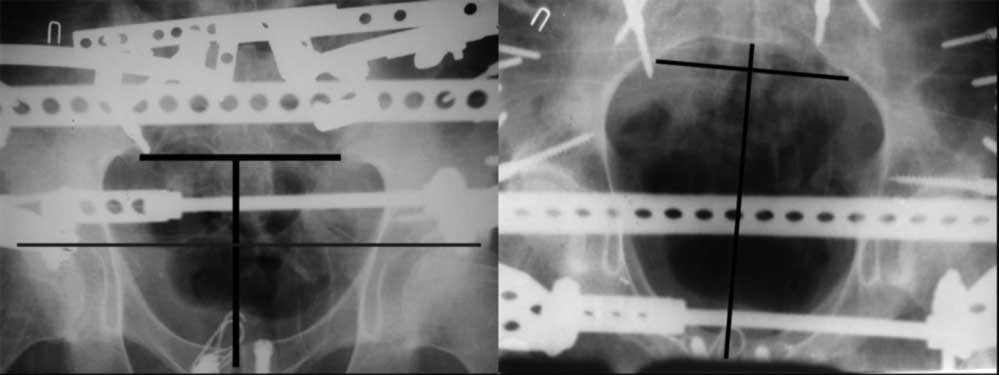

Дорогой Андрей. Мы имеем дело с комбинированной (ротационно и вертикально) нестабильностью таза со смещением правого гнемипелвиса. При таких переломах, фиксация только переднего полукольца вне зависимости от метода фиксации, как уже было сказано Djoldas Kuldjanov, M.D., не может создать адекватной фиксации. И перелом пластины был вполне ожидаемым после активизации пациента. Смещение сохраняется, и по-видимому не 2 см., а все 4, если не более. Разница всего (+2 см) по конечностям как вы указываете, скорее скомпенсировано позвоночником и протезом. Дополнительные снимки или КТ исследование помогли бы уточнить степень смещения с точностью до мм., выявить перелом поперечного отростка пятого поясничного позвонка, или помимо разрыва правого крестцово-подвздошного сочленения выявить перелом боковой массы крестца справа и т.д. При возможности, конечно, все это желательно сделать. Но мало что изменится с практической точки зрения, т.к. задача - это низведение репозиция и надежная фиксация правого гемипелвиса. Учитывая плачевный опыт стержневого аппарата, давность травмы совершенно очевидно, что поставленная задача достижима при открытой репозиции и одномоментной фиксации переднего полукольца с артродезированием правого крестцово-подвздошного сустава. Операция выполняется в положении больного на здоровом боку или полубоку из расширенного трансоссального подвздошно-пахового доступа с переходом на лонное сочленение доступом по Pfannenstiel. Указанный доступ обеспечивает подход к крестцово-подвздошному сочленению как спереди так и сзади. После артродезирования выполняется синтез лонного сочленения. Клинический пример

Пациентка С.26 лет. Травма за 6 месяцев до поступления

Укорочение правой нижней конечности до 10см

23.09.2003. Одновременный остеосинтез переднего и заднего тазовых полуколец

Результат через 10 дней

и 8месяцев после операции

> Результат через 10 дней и 8месяцев после операции

Да, забыл сказать - отличная работа, искренне восхищаюсь. Кость рубите по Judet (немного не разобрался по рисунку)?

Маленькая иллюстрация (около 5 лет после травмы). Результат плохой - укорочение, хромота, периодически боли в спине, но больной отказывается от операции, видимо, не так все трагично.